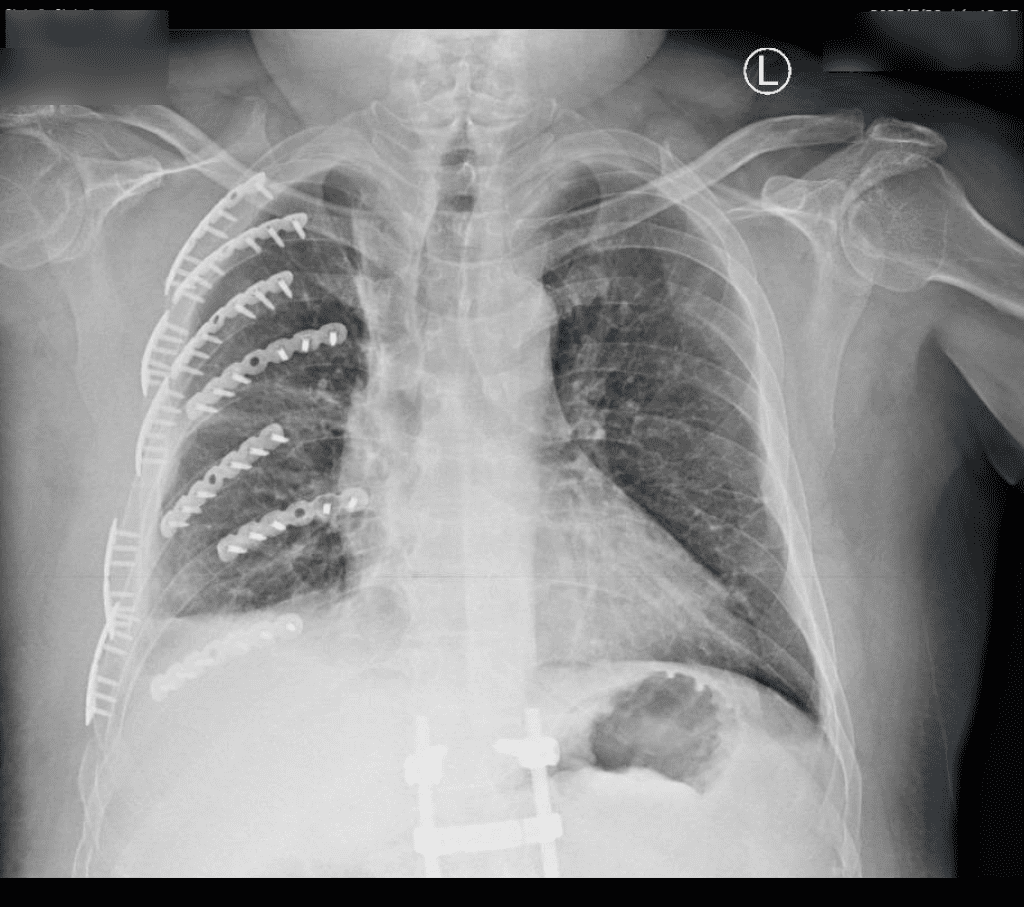

圖說:陳姓工人斷了14處肋骨經部彰重建恢復良好,不再因胸痛,已能開懷大笑

彰化醫院胸腔創傷微創重建中心主任林聿騰表示,患者身體強壯,在強烈撞擊下,還是有8根肋骨斷裂了14處,血胸及胸廓變形,造成嚴重錯位的「連枷胸」,也就是相鄰3根以上的肋骨骨折,吸氣時損傷部位下陷,疼痛指數可說是超過忍受範圍,如果未積極治療,恐引發肺炎、呼吸衰竭等併發症,因此先進行胸腔微創手術,將病人的痛楚降到最低。

林聿騰說,患者整個變形的胸腔透過3D胸廓重組影像定位,只在胸側及背後開了2個小傷口,以鈦合金骨板及骨釘進行肋骨固定,穩定整個胸腔,讓患者可以正常呼吸,接著再進行骨科手術。骨科醫師陳柏辰指出,患者右手橈骨在大力撞擊下,造成10多塊碎片的粉碎性骨折,他以鈦合金鋼板固定,骨盆腔骨折則保守治療,降低患者疼痛。